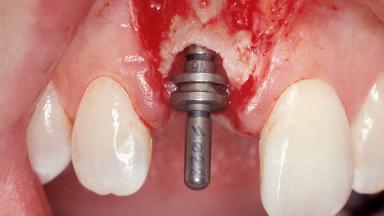

A 30-year-old female patient was referred to the office for the treatment of tooth 11. Her chief concern at the initial visit was to inquire, “Why is my tooth pink?” Upon clinical examination, it was determined that tooth 11 had a previous history of trauma and that the clinical crown had become noticeably pink in color as a result of internal resorption. This diagnosis was confirmed radiographically, indicating a large radiolucency involving the central and distal portions of the clinical crown. It was determined that restoration of this tooth was not possible, and that extraction was indicated. The presence of a mid-line diastema, which the patient wanted to reproduce, directed the treatment plan for tooth replacement utilizing a dental implant.

Placement Protocol Immediate implant placement

Tooth Site Maxillary incisor or canine

Socket Morphology Single-root socket

Socket Integrity Sufficient, with intact bone walls